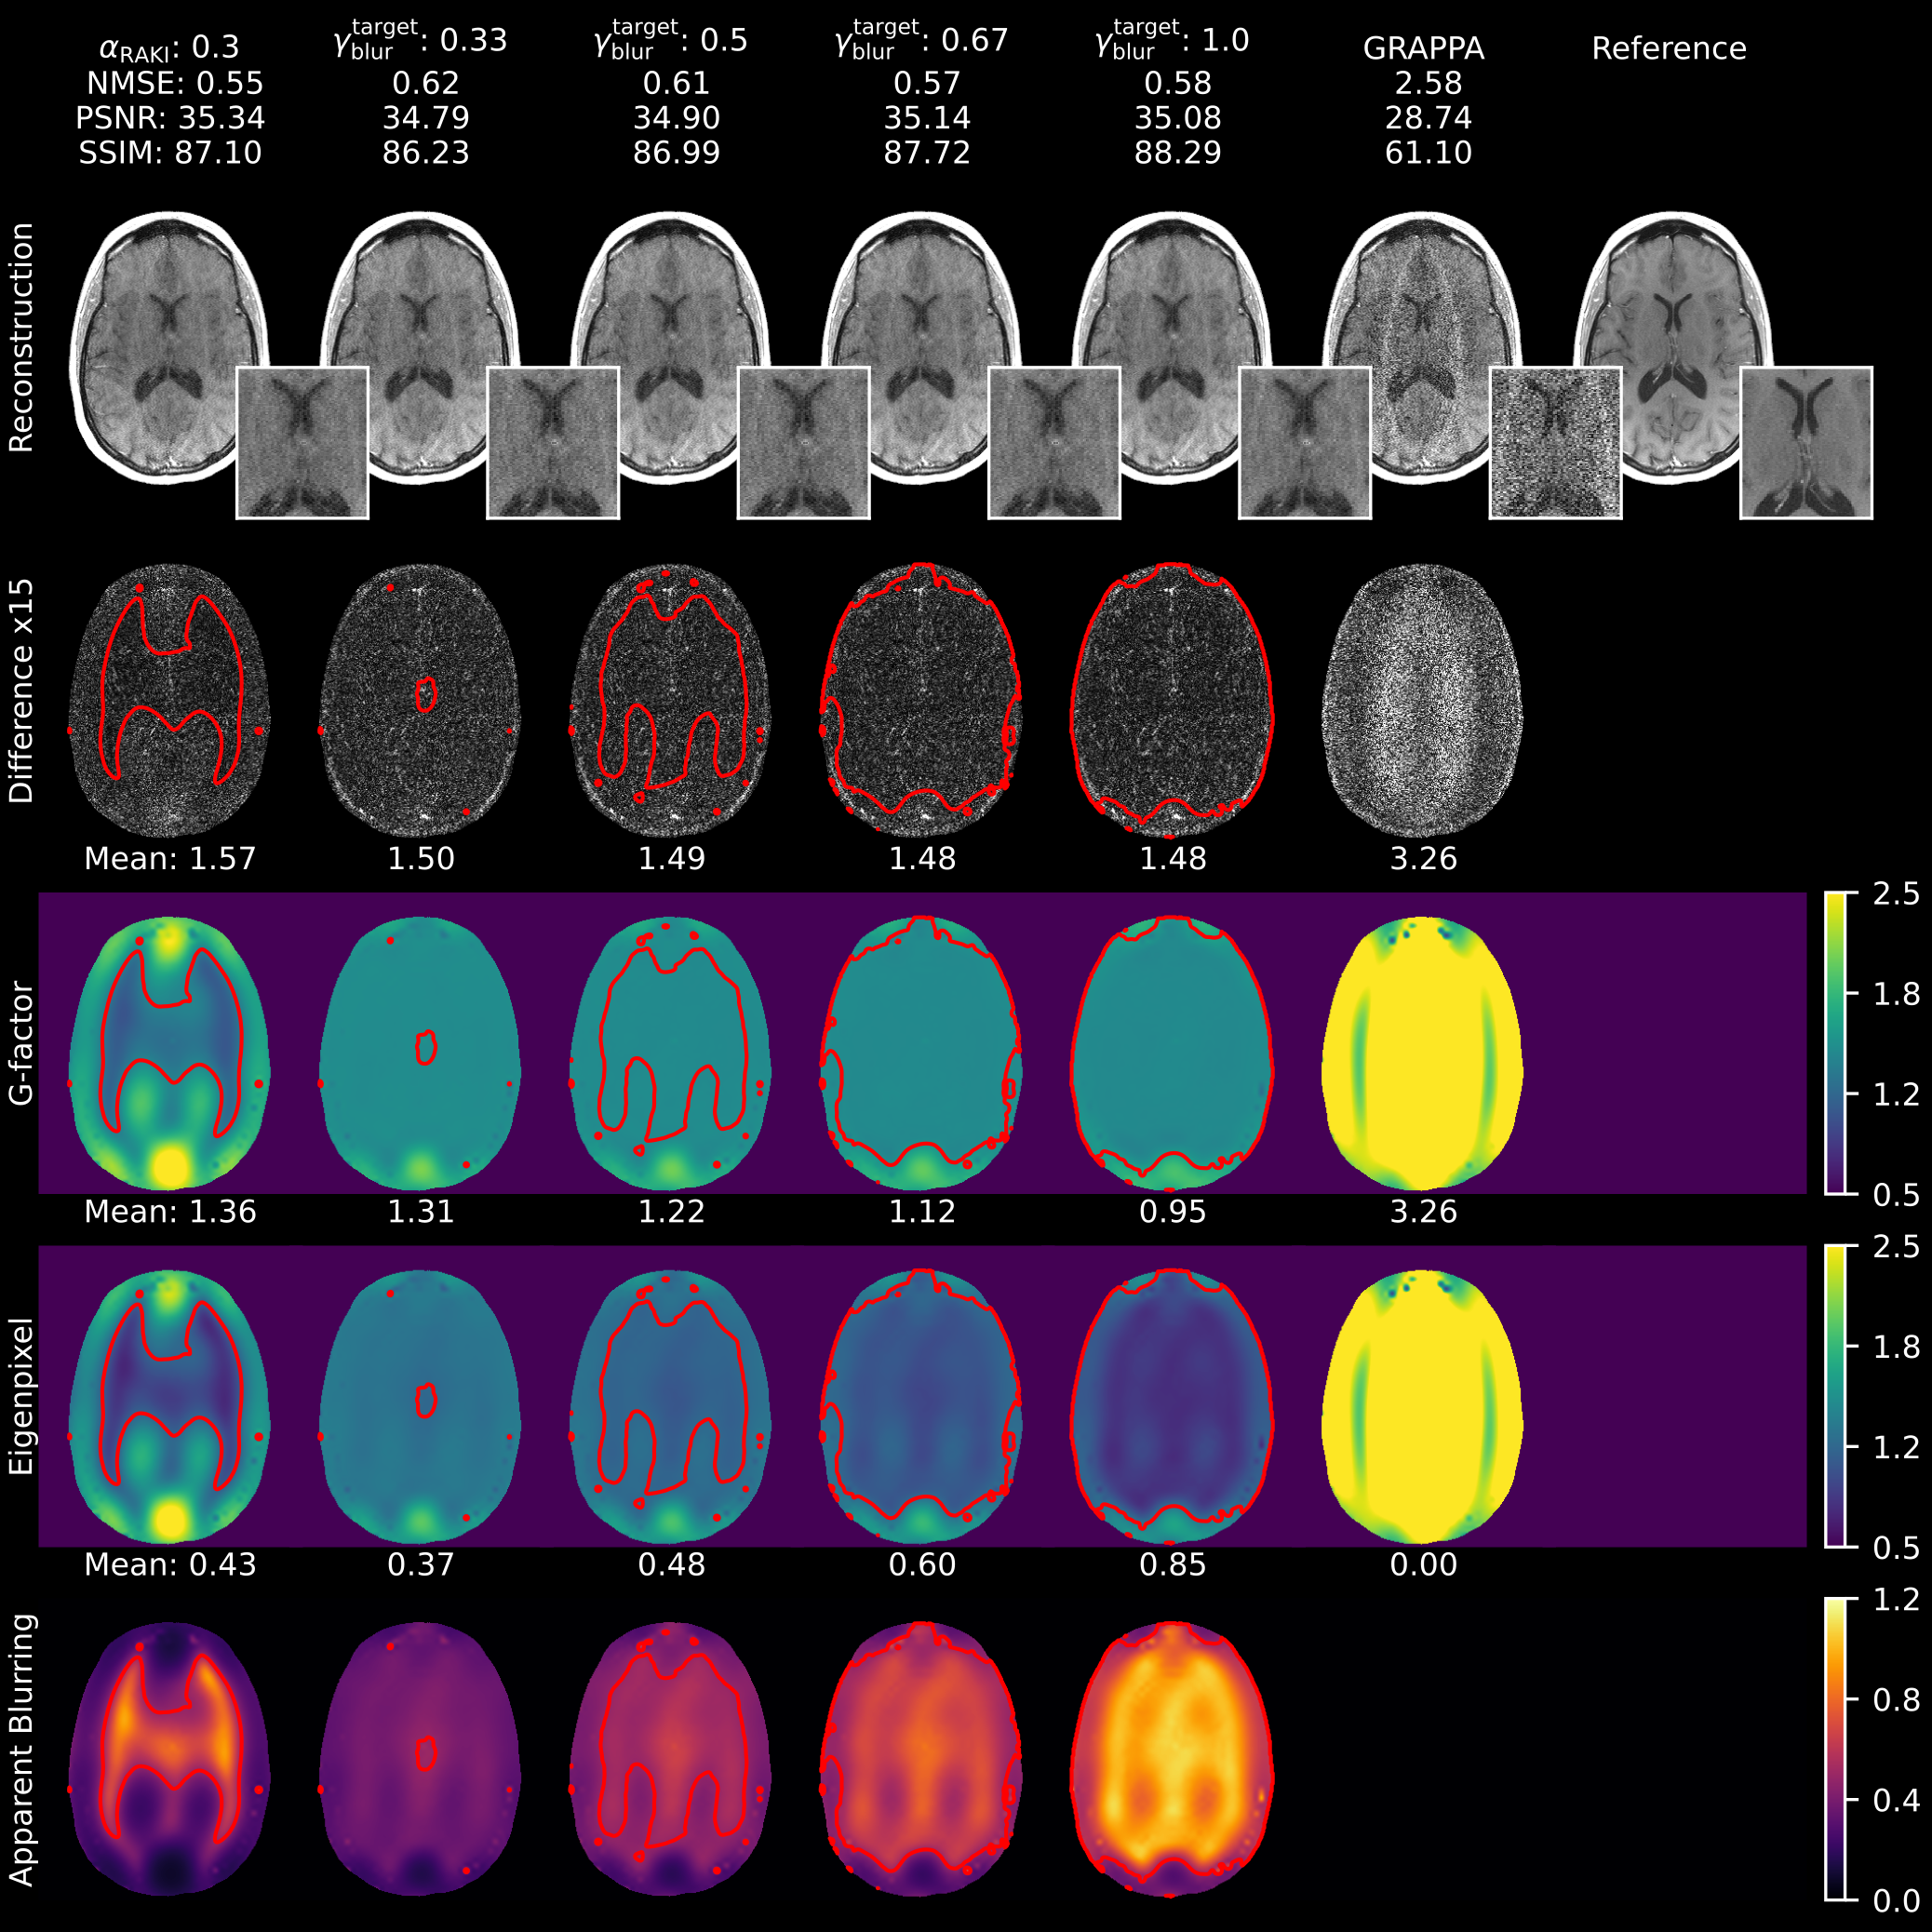

4.2 Impact of variance regularization

Figure 7 illustrates the impact of varying apparent blurring levels at a constant g-factor target for GIF-RAKI (R=5R=5). Compared to standard RAKI, GIF-RAKI variance regularization produces more homogeneous variance maps by eliminating spatially oscillating noisy and oversmoothed regions. While higher apparent blurring targets improve quantitative metrics, they also increase the perception of image smoothness. Under constant g-factor constraints, the loss function gfactor+blurG\mathcal{L}_{\text{gfactor+blur}}^{\scriptscriptstyle\text{G}} effectively shifts the balance between linear and nonlinear variance components. Similar performance is observed for GIF-iRAKI at a higher 6-fold acceleration (Figure 8). Supplementary Figures 1 and 2 demonstrate the effect of varying g-factor levels at a constant apparent blurring target for GIF-RAKI and GIF-iRAKI (R=5R=5), respectively. As the g-factor rises, increased pixel contamination is required to maintain a constant level of apparent blurring. Notably, apparent blurring remains dominant even at elevated g-factor levels.

Variance regularization beneficially influences image quality. Minimizing the g-factor imposes an absolute constraint on the overall noise level, while the apparent blurring regularization balances the ratio between linear and nonlinear components within the total variance (Figure 7 and 8, Supplementary Figure 1 and 2). These observations justify a regularization strategy that prioritizes achieving specific apparent blurring targets at lower g-factor levels. For the joint g-factor-apparent blurring loss gfactor+blurG\mathcal{L}_{\text{gfactor+blur}}^{\scriptscriptstyle\text{G}} specifically, targets of γgfactortarget=1.25\gamma_{\mathrm{gfactor}}^{\mathrm{target}}=1.25 and γblurtarget=0.5\gamma_{\mathrm{blur}}^{\mathrm{target}}=0.5 were proved to be effective for conservative variance regularization at the group level as well (Figure 10). The higher apparent blurring level imposed by variance regularization translated into elevated SSIM scores compared to RAKI. This indicates the metric’s inherent bias toward image smoothness, as previously documented Mason et al. [2020-04], Pambrun and Noumeir [2015]. Furthermore, gfactor+blurG\mathcal{L}_{\text{gfactor+blur}}^{\scriptscriptstyle\text{G}} encourages homogeneous variance maps and prevents the eigenpixel variance from dropping below one, thus avoiding non-physical scenarios. Simultaneously, it suppresses the network’s tendency to replace noisy regions with nonlinear signal mixing from other pixel locations, thereby reducing the central blurring hotspots (Figure 9).